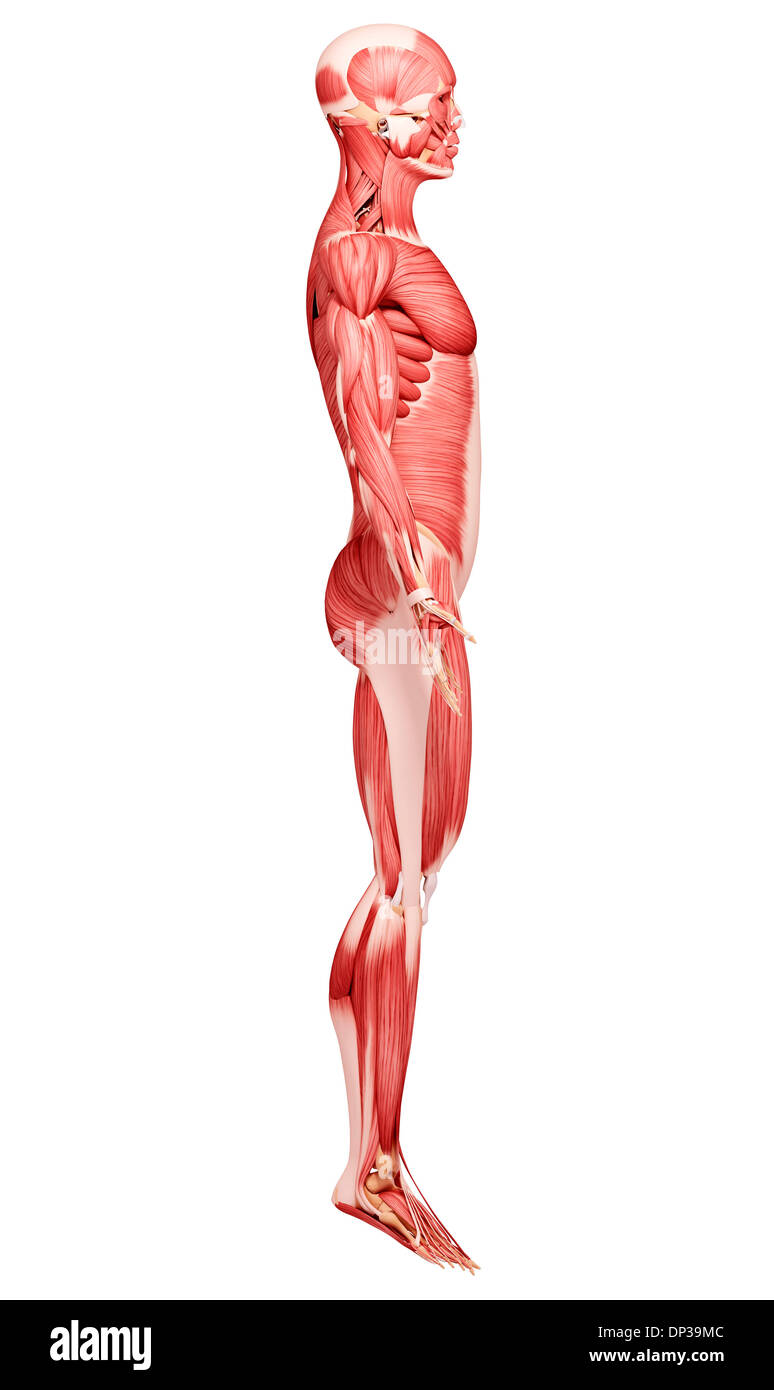

Musculature, artwork Banque D'Imageshttps://www.alamyimages.fr/image-license-details/?v=1https://www.alamyimages.fr/musculature-artwork-image65229644.html

Musculature, artwork Banque D'Imageshttps://www.alamyimages.fr/image-license-details/?v=1https://www.alamyimages.fr/musculature-artwork-image65229644.htmlRFDP3D24–Musculature, artwork